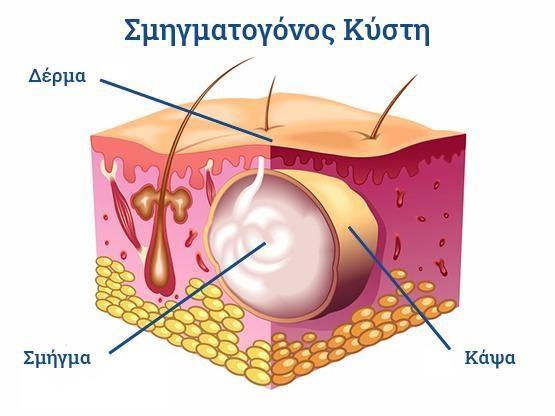

Ο Γενικός Χειρουργός Λιάγκος Γεώργιος MD PhD εκτελεί τις επεμβάσεις Λαπαροσκοπικά, Ενδοσκοπικά, Ανοιχτά Ελάχιστα Επεμβατικά και με Laser. Η θεραπεία εξατομικεύεται σε κάθε ασθενή ανάλογα με τις ανάγκες του. Αναλαμβάνει περιπτώσεις όπως κήλες και κοιλιοκήλες (αντιμετώπιση βουβωνοκήλης, αντιμετώπιση ομφαλοκήλης, θεραπεία επιγαστρικής κήλης, κήλη των αθλητών (Σύνδρομο κοιλιακών προσαγωγών), αντιμετώπιση μετεγχειρητικής κήλης, θεραπεία Μηροκήλης), πέτρες στη χοληδόχο κύστη, λαπαροσκοπική χολοκυστεκτομή, αντιμετώπιση Κύστη Κόκκυγος με λέιζερ (laser), παθήσεις πρωκτού, χειρουργική laser σύγχρονων κυκλικών ινών (αιμορροΐδες αντιμετώπιση, θεραπεία αιμορροϊδων με laser (LHP), αφαίρεση αιμορροΐδων με υπερήχους (HALL-RAR), χωρίς Χειρουργείο με ελαστικούς δακτυλίους (Τεχνική BARON-RBL), θεραπεία ραγάδας πρωκτού (Ραγάδα δακτυλίου), θεραπεία περιεδρικού συριγγίου, θεραπεία περιεδρικού αποστήματος, κονδυλώματα πρωκτού Θεραπεία, δερματικό ράκος (Skin tag) εκτομή, αντιμετώπιση Kνησμού, καρκίνος πρωκτού θεραπεία), παθήσεις Δέρματος, χειρουργική με laser CO2, αφαίρεση μορφωμάτων δέρματος - βιοψίες, αφαίρεση ελιάς (Σπίλου), σμηγματογόνος κύστης θεραπεία, αφαίρεση λιπώματος, είσφρυση όνυχος χειρουργείο, καρκίνος δέρματος θεραπεία, οξεία σκωληκοειδίτιδα, παθήσεις Λεπτού και Παχέος Εντέρου, ειλεός λεπτού εντέρου, εκκολπωμάτωση (Εκκολπωματίτιδα) σιγμοειδούς, καρκίνος παχέος εντέου, κολοστομίες, port χημειοθεραπείας κ.α. εξυπηρετώντας Παγκράτι και γύρω περιοχές.